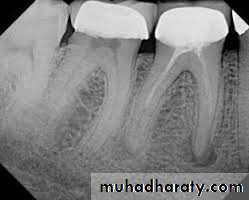

Standardized Technique

Standardized tech. Illustration